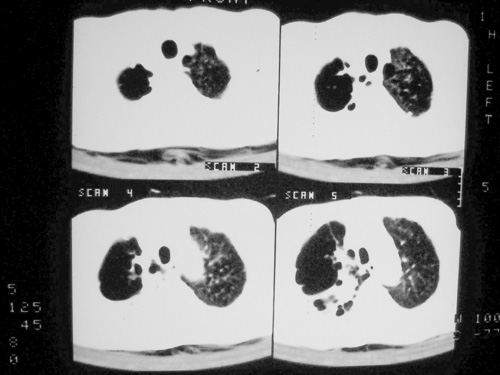

老年男性,70岁。煤矿工人20年。一周前咳嗽、发烧,拍x片考虑矽肺可能。始终咳嗽行ct检查,发现弥漫性病变,似感染但密度很高,细支气管肺泡癌无法排除,请老师给予指点。

一般矽肺多为双肺融合状,团块状高密度结节影.并散在多处小结节影.可这个病人只表现在单肺,并没有融合结节影.一周前的x片没显示大片高密度影,可定位扫描时(图象忽略传了),右肺已经清晰显示大片高密度影.作比较感觉是新病灶.可实际表现又不象,所以才拿来让各位老师看看.